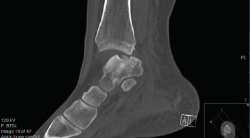

Las clasificaciones de las LOC se basan principalmente en sus características radiográficas. El sistema original de clasificación radiográfica fue desarrollado en 1959 por Berndt y Harty, y basado en proyecciones simples; posteriormente, Loomer añadió el grado V (Tabla 1)(16,17). Antes de esta adición, la clasificación de Berndt y Harty solo abordaba lesiones agudas o fracturas osteocondrales (grados I-IV), mientras que el tipo V (lesión quística) es más característico de las lesiones crónicas (Figura 1).

Figura 1. Radiografía que muestra una lesión osteocondral en la zona medial de la cúpula articular.